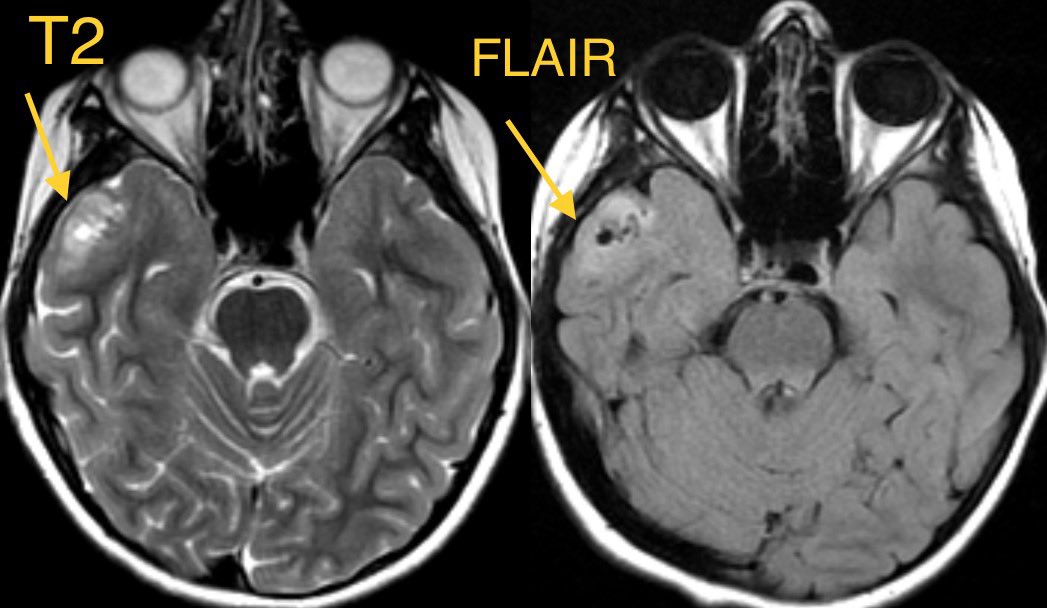

2️⃣DNET

▶️Cortically based mass in children and young adults presenting with long-standing seizures

▶️Most frequently occurs in temporal and frontal lobes

▶️Classically presents as a well demarcated cortically based “BUBBLY” mass with HYPERINTENSE RIM AROUND CYSTS ON FLAIR ImageImageImage

▶️Usually there is NO ENHANCEMENT (though can have punctate or ring enhancement). However, when enhancement is seen, consider the possibility of more aggressive tumors.

▶️Companion case below of another DNET ImageImageImage